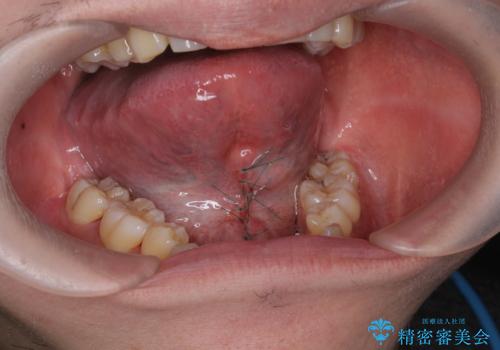

舌小帯の形成は10分程度で終わる小手術です。

手術を受ける前は怖かったけれど、長年悩みの種であった滑舌が改善できたと喜んでいただくことができました。